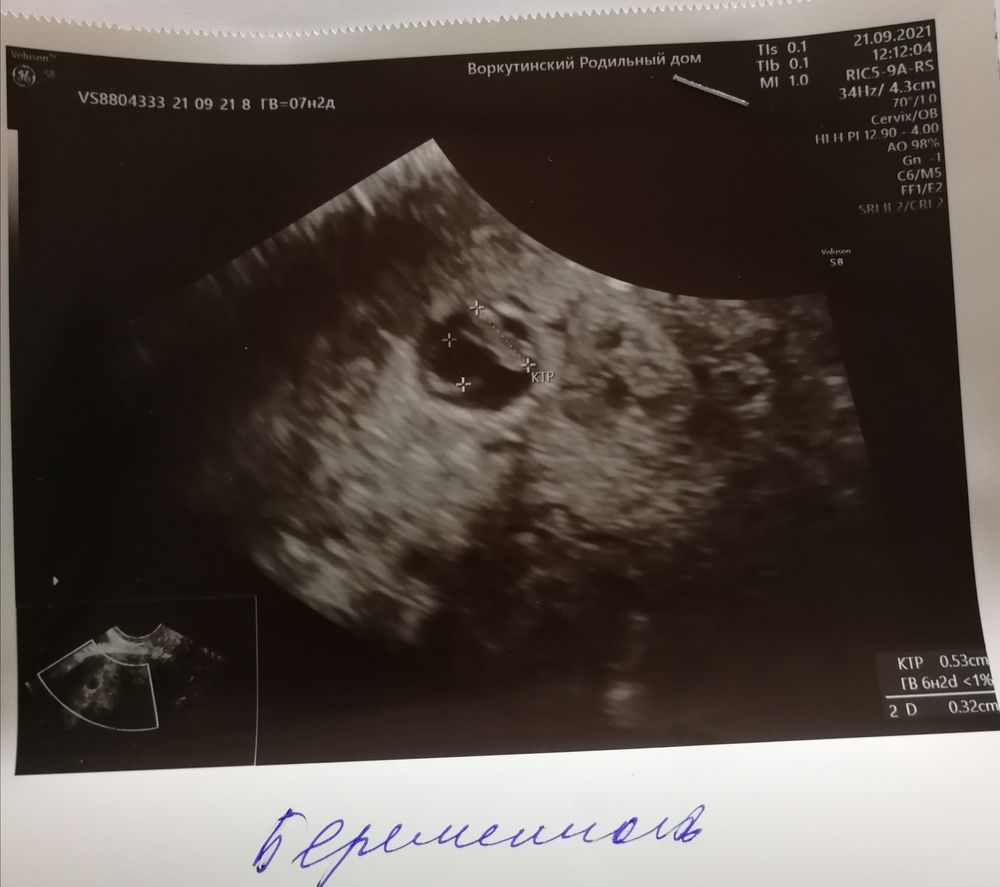

увидела только ПЯ 13,5 мм и все

но мне кажется я что-то вижу!!! Поддержку не отменила, буду ждать!!! Записалась завтра на экспертное узи! Посмотрите, видите что-нибудь?

На фото пусто, шанс мал, так как нет даже желточного мешочка☹️ Хотя он раньше эмбриона появляется, а потом на «колечке» появляется «бриллиант»- эмбрион. Не хочу расстраивать, но вряд ли что-то появится

Во первых "срочно" на МА точно не нужно. Если это первое УЗИ, обязательно переделать через неделю (а лучше сейчас проверить у другого узиста и динамику смотреть у него же потом). По фото действительно пусто сейчас. То что вы обвели на фото в комментариях это уже за пределами ПЯ. Но анэмбриония ставится при размерах ПЯ 20-25 мм, так что у вас шансы ещё есть, что все появится, чего вам и желаю 🙌